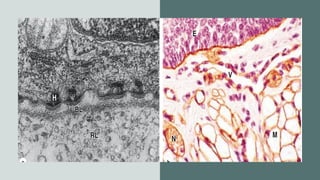

• With the transmission electron microscope (TEM) two

parts of the basement membrane may be resolved.

• Nearest the epithelial cells is an electron-dense layer,

20-100 nm thick, consisting of a network of fine fibrils

that comprise the basal lamina and beneath this layer

is a . more diffuse and fibrous reticular lamina.